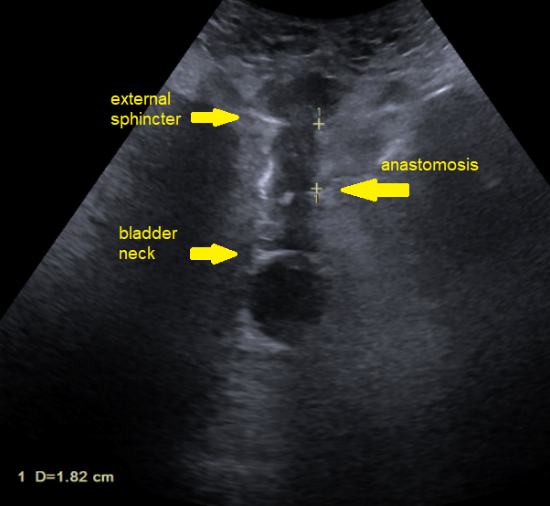

His pathology revealed Grade Group 5 (Gleason 5+4), pT3b, Nx, Mx prostate cancer with involvement of the left neurovascular bundle and seminal vesicle, with negative surgical margins. Transperineal ultrasound was performed prior to Foley catheter removal at day five (Figure 7).

- Robotic-assisted radical prostatectomy featured maximal urethral length preservation and right-sided intra-fascial nerve sparing, with 1.82 cm preserved to the anastomosis and 3.6 cm to the bladder neck; he was discharged same-day.